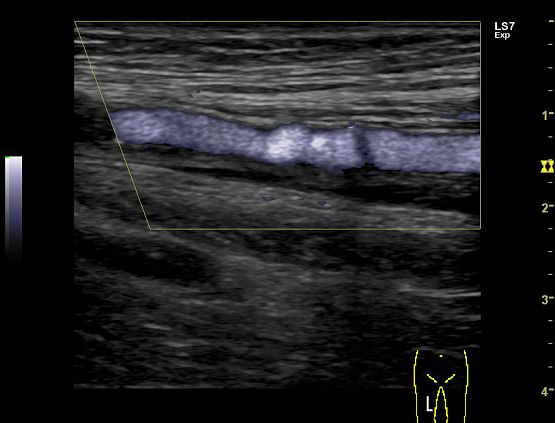

Клинические изображения

- B-Flow / Color B-Flow - режим недопплеровской визуализации кровотока

Ультразвуковой аппарат LOGIQ S7 XDclear предназначен для использования специалистами из различных областей диагностики. Его расширенный функционал включает такие возможности как B-Flow — недопплеровская технология отображения кровотока в B-режиме, компрессионная эластография (качественная и полуколичественная), количественный анализ васкуляризации, функцию В-Steer+ — изменение угла наклона УЗ луча в B-режиме, 3D/4D диагностику и мультимодальную визуализацию.